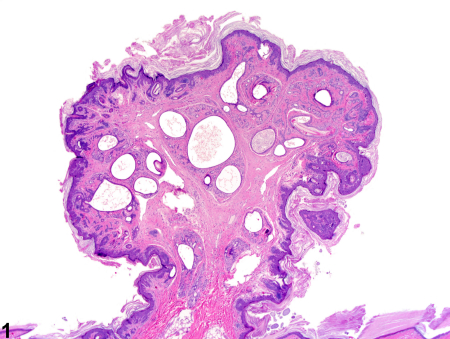

هامارتوما یک تومور غیرسرطانی (خوش‌خیم) است که از همان سلول‌های موجود در بافت اطراف ساخته شده است، اما این سلول‌ها و بافت‌ها به صورت نامنظم و بی‌نظم تومور می‌کنند. بیشتر هامارتوماها هیچ علامتی ایجاد نمی‌کنند و جدی نیستند. اگر هامارتوما مشکلی ایجاد کند، معمولاً با جراحی برطرف می‌شود.

هامارتوما (تلفظ: هَم-آر-تُو-ما) یک تومور شبه‌توموری است که می‌تواند در هر جای بدن ظاهر شود. وقتی مردم کلمه «تومور» را می‌شنوند، اغلب به سرطان فکر می‌کنند، اما هامارتوماها سرطان نیستند. آن‌ها فقط ترکیبی از همان سلول‌ها و بافت‌هایی هستند که به طور طبیعی در آن ناحیه از بدن وجود دارند، اما به صورت نامنظم تومور کرده‌اند.

• هامارتومای ریوی (در ریه‌ها)

شایع‌ترین هامارتومای خوش‌خیم ریه است (حدود ۷۰–۸۰٪ تومورهای خوش‌خیم ریه).